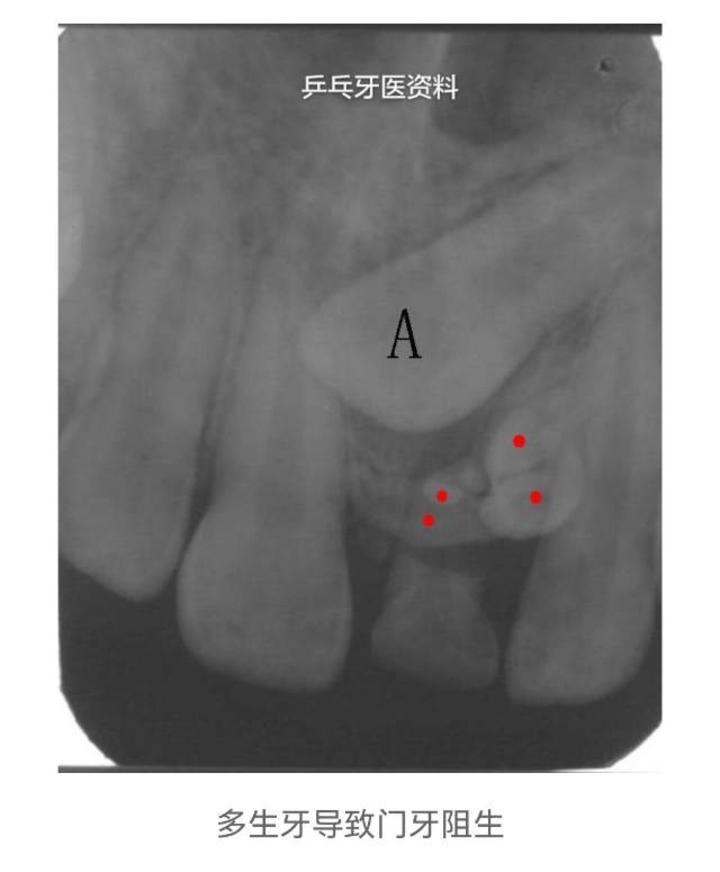

3.恒牙、乳牙阻生,不能萌出